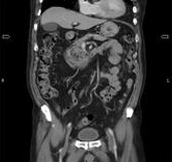

3D volume rendering reconstruction for separation of different soft tissues.

Tumor volume calculation in soft tissue.